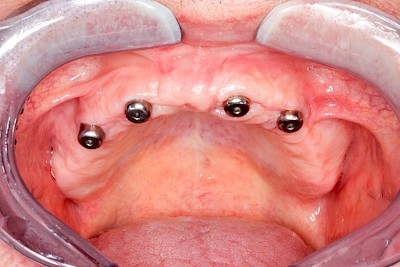

Bei herausnehmbaren Prothesen werden Implantate eingesetzt, um den Halt und den Tragekomfort der Prothesen zu verbessern. Dazu kommen verschiedene Verbindungselemente zum Einsatz:

- Kugelköpfe

Neben rein implantat-getragenen zahnärztlichen Versorgungen werden bei herausnehmbaren Prothesen Implantate auch in Sinne einer "strategischen Pfeilervermehrung" ergänzend zu eigenen Zähnen zur Verankerung eines Zahnersatzes genutzt.